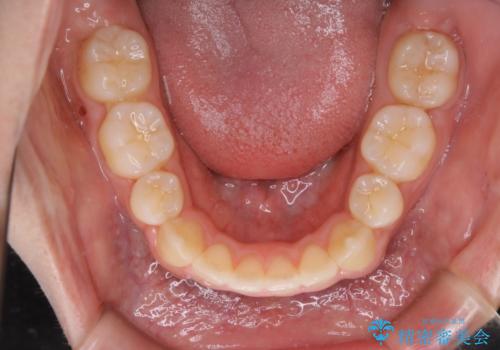

- 2年6ヶ月

親知らずと、前から4番目の歯を抜歯してワイヤー装置による矯正治療を行いました。

人前に出ることが多いため、当初は目立たない装置をご希望されていましたが、歯の移動距離が大きいため効率よく歯を動かせる表側の装置での治療をお勧めしました。すれ違ってしまっていた奥歯もしっかり治すことができました。